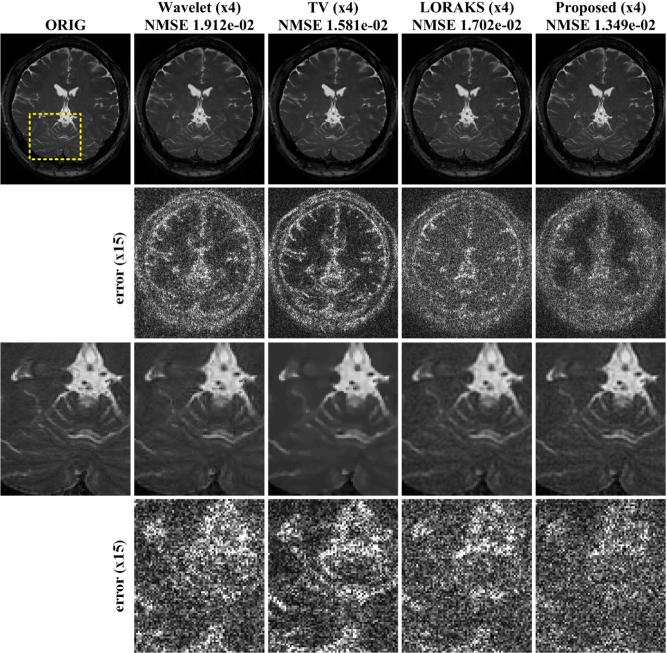

Refer to caption

Figure 4: Parallel imaging results using GRAPPA, SAKE, SAKE with ESPIRiT and the proposed method at 8 fold acceleration. The second row shows the difference images. Areas with systematic artefacts are indicated by yellow arrows. Note that GRAPPA requires ACS lines, so with the additional 50 samples along ACS, the effective downsampling ratio was 4.785.

Next we compared our parallel imaging results with those of the existing approaches for additional multichannel brain data set. The NMSE results in Fig. 4 showed that ALOHA was most accurate. From the difference images at the second row of Fig. 4, we observed that proposed method provided reconstruction results more accurately than other algorithms. In SAKE, the structures were distorted around the inner skull and the boundaries of tissues. In SAKE with ESPIRiT, overall reconstruction errors were higher than those from ALOHA and there were still remaining errors around the skull. The reconstruction time was 22.2sec with our preliminary GPU implementation of ALOHA, which attained a speed-up factor of 5 compared to CPU implementation. On the other hand, the computational time for MATLAB version of GRAPPA, SAKE, and SAKE+ESPIRiT were 9s, 320.4s, and 21.6s, respectively.